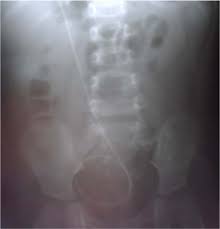

Plain X Ray Of Abdomen Shows The Tip Of The Vp Shunt Was Curling Over Download Scientific Diagram